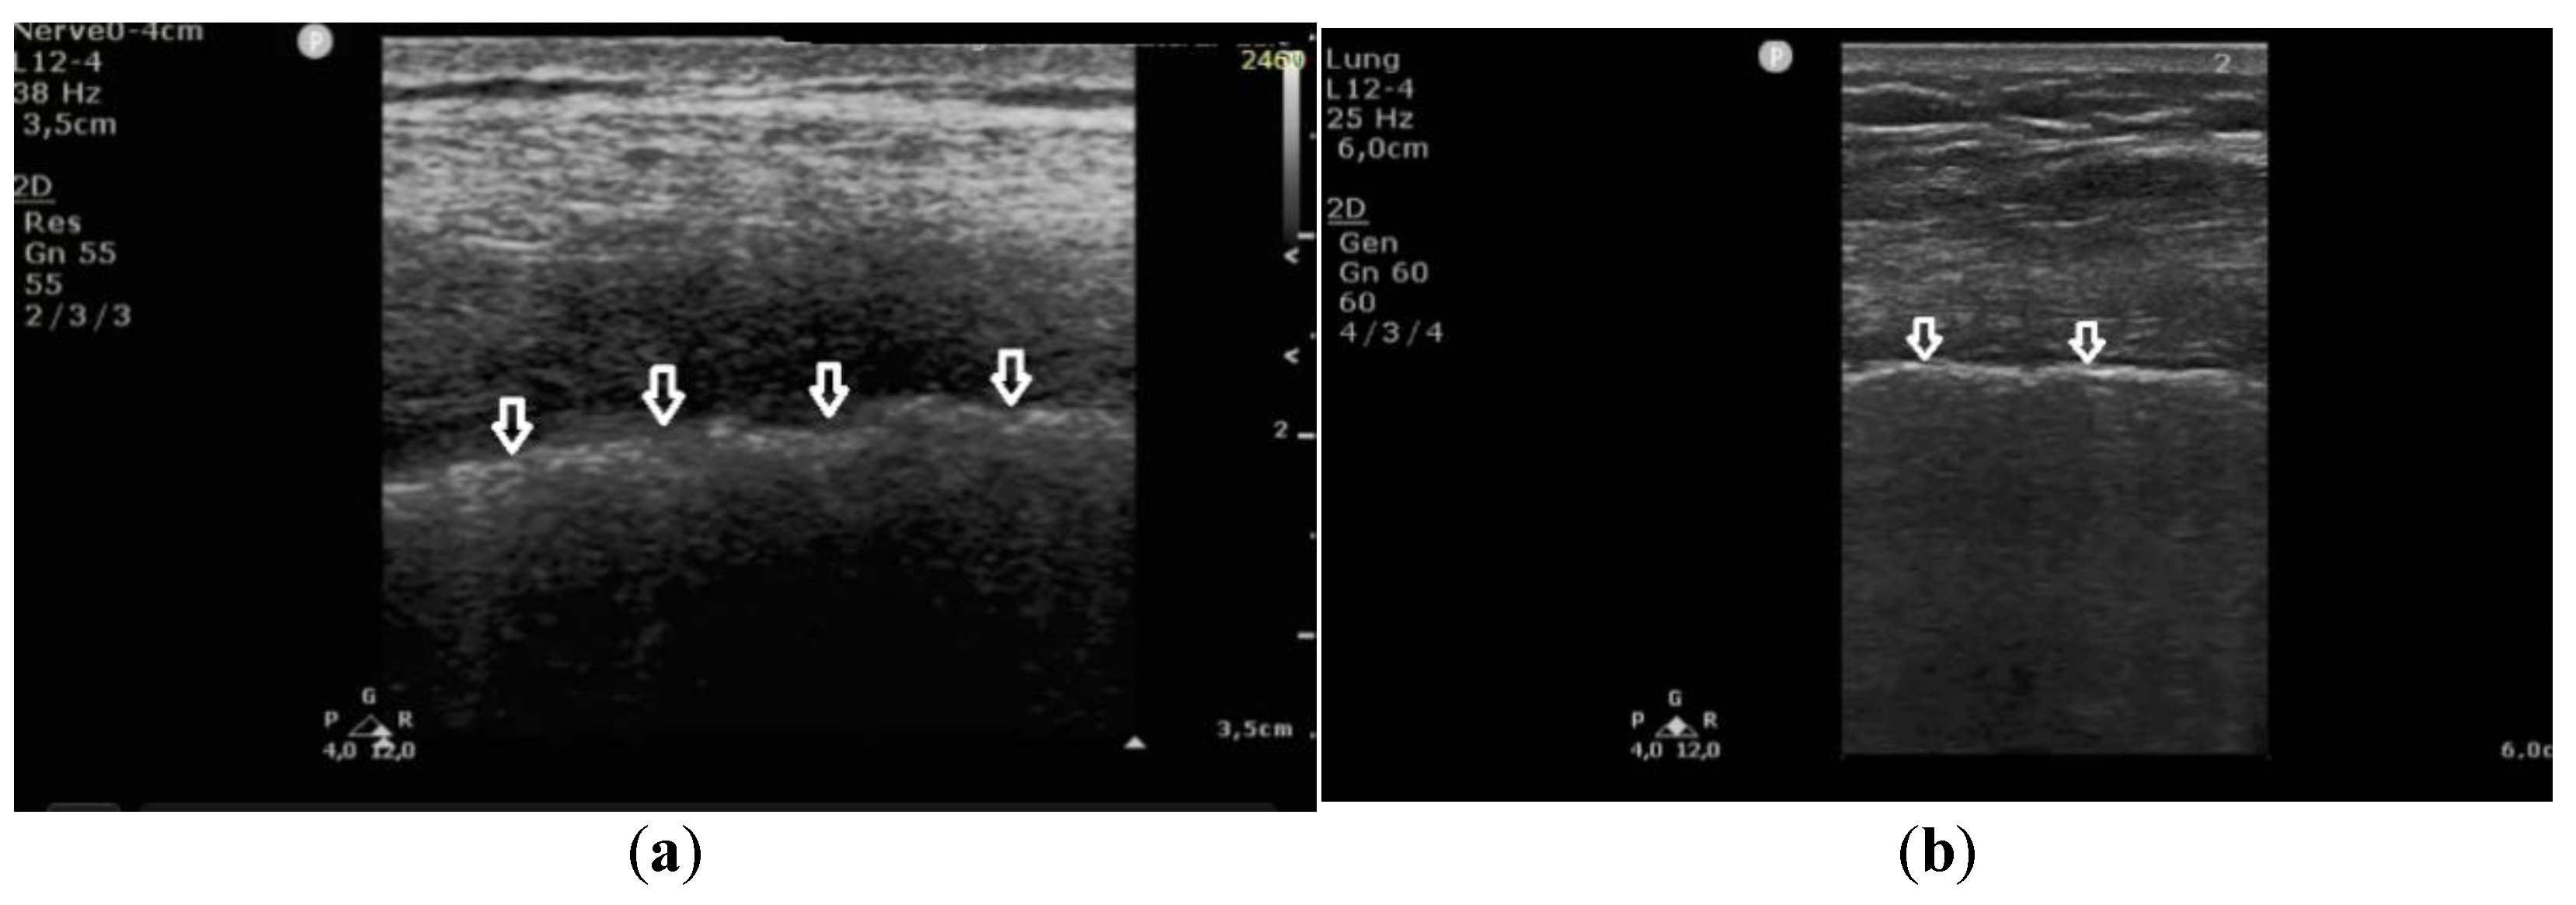

In patients with cardiogenic pulmonary edema, at the frequency of 6 MHz, B-line artifacts were present in 62% of the evaluated points, and Z-lines in 24%, including the mixed profile of B and Z in 16% of the examined areas (Figure 2). Consequently, the change in frequency leads to a change in the profile of vertical artifacts, whereas this phenomenon is much more frequent in patients with pulmonary fibrosis secondary to ILD. Collected data are demonstrated in Table 2.

Figure 2. Cardiogenic pulmonary edema; (a) B-lines at 2 MHz (white arrows), regular pleural line (black arrow), (b) B-lines at 6 MHz (white arrow), regular pleural line (black arrow).

Figure 3. Linear transducer used for the evaluation of pleural line abnormalities: (a) irregular, blurred pleural line (white arrows), coarse in appearance, in pulmonary fibrosis; (b) regular pleural line, with preserved echogenicity (white arrows), in pulmonary edema.